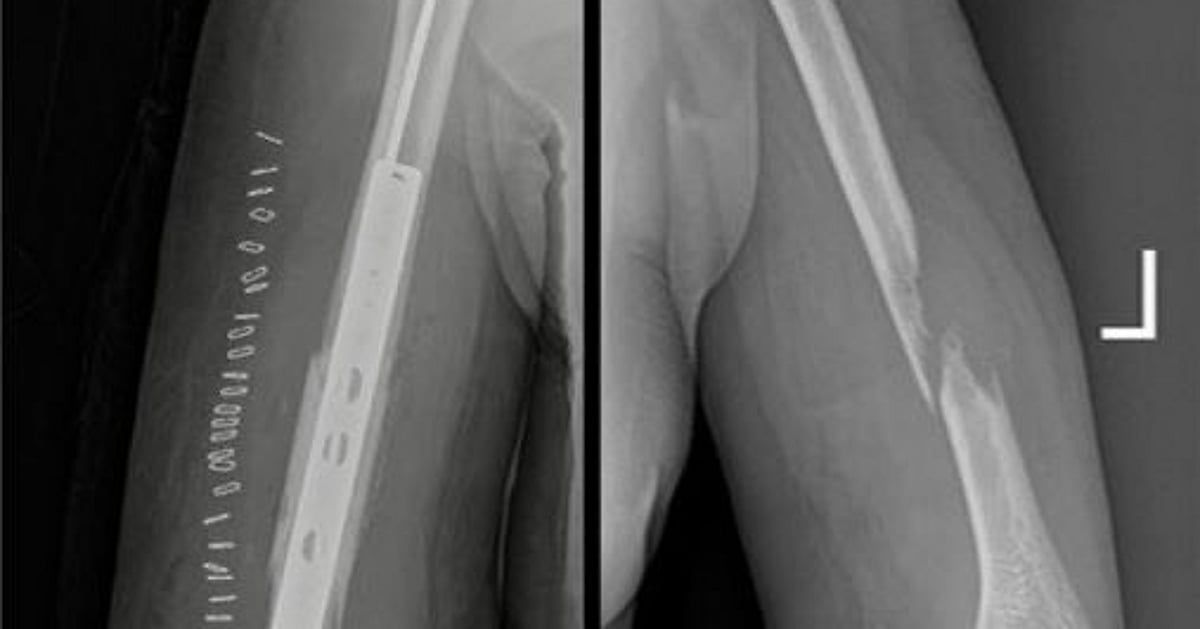

وكانت المريضة قد وصلت إلى المستشفى الرئيسي وهي تعاني من ورم سرطاني تسبب في تآكل جزء من عظمة العضد الأيمن، ما أدى إلى ضعف شديد في حركة اليد وقيود كبيرة في أداء المهام اليومية.

وأوضح "تجمع المدينة المنورة الصحي" أن الحالة جرى تشخيصها بدقة باستخدام أشعة الرنين المغناطيسي، وأُكد التشخيص من خلال خزعة نسيجية، مبينًا أن خطورة الحالة وحساسيتها تطلبت تدخلاً جراحيًا عالي الدقة.

وتمكّن الفريق الطبي من استئصال الجزء المتآكل من العظم، وإعادة بناء الفراغ باستخدام إسمنت طبي ومتثبتات معدنية، مع الحفاظ التام على الأعصاب والشرايين الرئيسية دون أي ضرر.

وأشار التجمع إلى أن المريضة تماثلت للشفاء وأصبحت قادرة على استخدام يدها بشكل طبيعي، بعد أن كانت تعاني من شبه شلل، مؤكدًا أن هذا الإنجاز يُعد إضافة نوعية في سجل النجاحات الطبية بالمنطقة، ويعكس جاهزية وكفاءة الكوادر الصحية في تقديم رعاية متقدمة وفق أعلى المعايير.